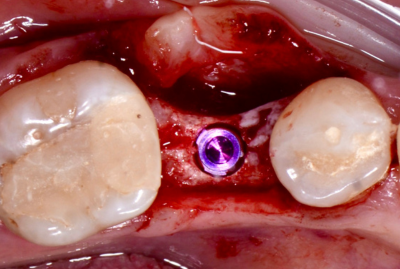

КЛинический случай максима хышова

ОДНОМОМЕНТНАЯ ИМПЛАНТАЦИЯ

Удаление зуба 26. Установка имплантатов VEGA+ в позиции 25 и 27.

✔️ В позицию зуба 27 установлен VEGA+ RV 4.6x10 mm. Получена первичная стабильность 20 Н/см. Установлен винт-заглушка

✔️В позицию зуба 25 установлен VEGA+ RV 4.1x14 mm. Получена первичная стабильность 50 Н/см. Установлен винт-заглушка.